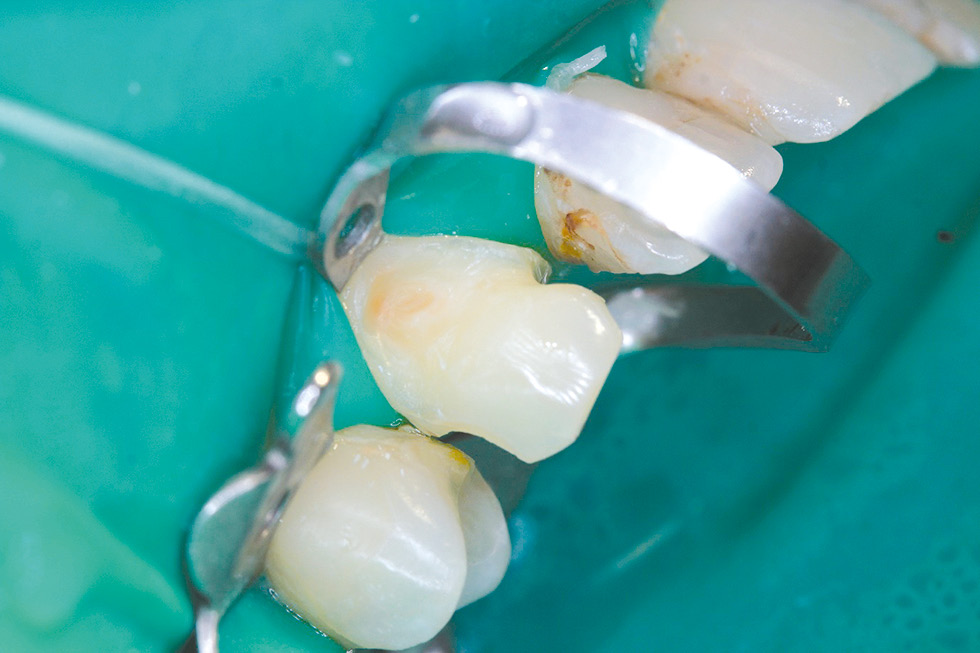

Treatment was carried out: under infiltration anesthesia Sol. Articaini–1 ml under water-air cooling, failed 1.3 restorations were removed, the vestibular surface was prepared for the manufacture of a direct composite restoration (Fig. 10). Enamel 1.3 was selectively etched, the OptiBond Universal adhesive system (Kerr) was applied, and direct restoration was performed using the OptiShade nanohybrid universal composite (Kerr) (Fig. 11, 12).

The use of the nanohybrid universal composite "OptiShade" (Kerr) made it possible to optimize the work in this clinical case. This material is presented in three shades (Light, Medium, Dark). To replace enamel and dentin, the Medium shade was used, which, thanks to the color substitution of sixteen shades, made it possible to successfully imitate the enamel and dentin of the tooth in terms of color. Due to the high adaptive characteristics and manipulation properties, the restoration of tooth 1.3 looks aesthetically pleasing. The time spent on restoration was reduced due to the use of a single shade of material.